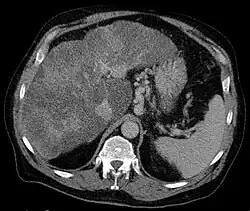

Gastric varices are dilated submucosal veins in the lining of the stomach, which can be a life-threatening cause of bleeding in the upper gastrointestinal tract. They are most commonly found in patients with portal hypertension, or elevated pressure in the portal vein system, which may be a complication of cirrhosis. Gastric varices may also be found in patients with thrombosis of the splenic vein, into which the short gastric veins that drain the fundus of the stomach flow. The latter may be a complication of acute pancreatitis, pancreatic cancer, or other abdominal tumours, as well as hepatitis C. Gastric varices and associated bleeding are a potential complication of schistosomiasis resulting from portal hypertension.

Secondly, patients with acute pancreatitis may present with gastric varices as a complication of a blood clot in the splenic vein. The splenic vein sits over the pancreas anatomically. Inflammation or cancers of the pancreas may result in a blood clot forming in the splenic vein. As the short gastric veins of the fundus of the stomach drain into the splenic vein, thrombosis of the splenic vein will result in increased pressure and engorgement of the short veins, leading to varices in the fundus of the stomach.